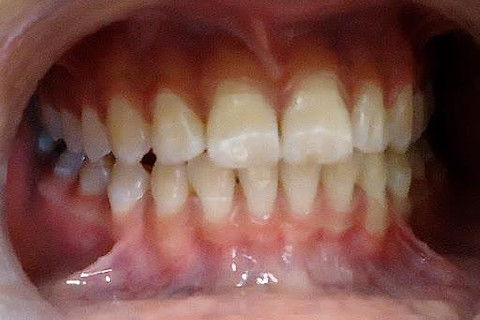

PACIENTE: feminina de 12 anos.

QUEIXA PRINCIPAL: dentes manchados.

DIAGNÓSTICO: FLUOROSE.

Fotos do caso

A fluorose é uma alteração que ocorre devido ao excesso de ingestão de flúor, durante a formação dos dentes. Ela se manifesta principalmente pela alteração da cor do esmalte, que pode assumir uma tonalidade esbranquiçada ou exibir pequenas manchas ou linhas brancas. Uma das maiores causas de fluorose é a pasta de dente com flúor, que muitas crianças engolem durante a escovação. O bochecho contendo flúor também pode contribuir, se for indicado para crianças que ainda não tenham o controle adequado da deglutição.

O período de maior risco para a ocorrência de fluorose é até os 6 anos de idade, quando estão se formando as coroas dos dentes da frente, pois se sabe que o maior problema da fluorose é quanto à estética.Crianças correm o risco de apresentar fluorose, porque ainda não sabem controlar a deglutição e nem cuspir adequadamente e acabam engolindo quantidade acima daquela segura para seu peso. Recomenda-se o uso de pastas de dente sem flúor, utilizando quantidade mínima de pasta na escova.